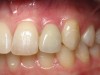

Figure 8  Clinical photograph of gingival recession resulting from excess cement around an implant crown in the maxillary right lateral incisor in a 24-year-old woman.

Figure 8